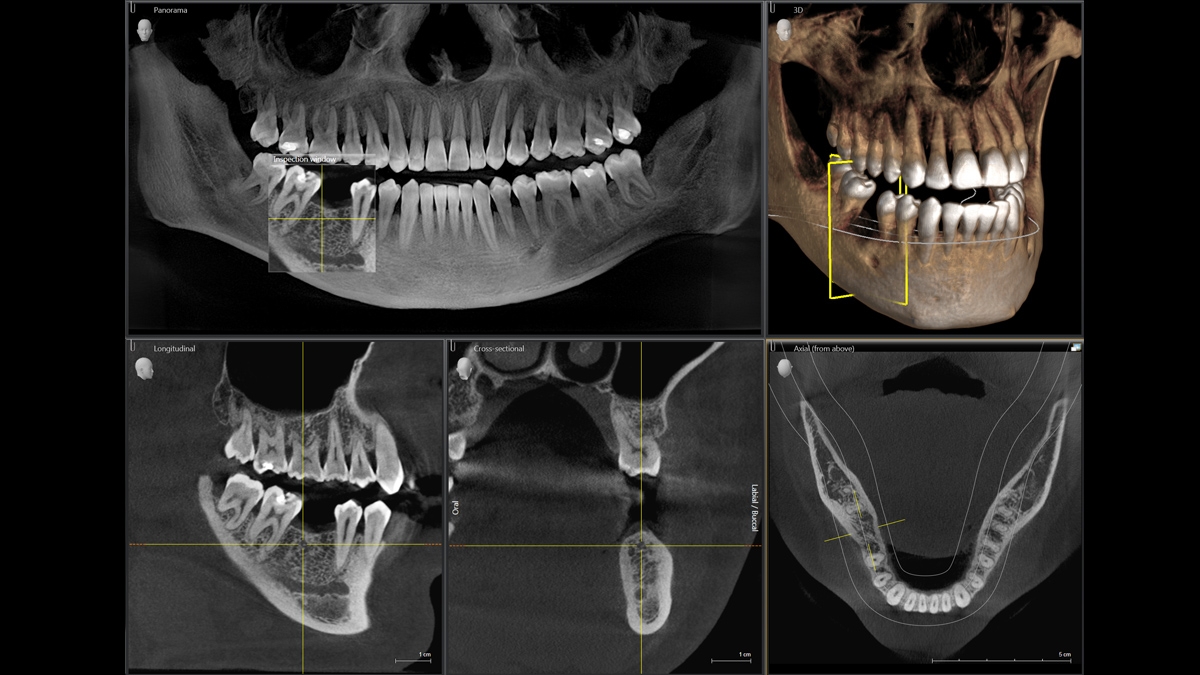

We developed a 10-point concept for easy patient positioning and X-ray imaging. Our concept is primarily about two things: high image quality and comfort for the patient and the assistant. This concept supports and provides the tools needed to ensure high-quality images for treatment analysis and focuses on ergonomics and comfort for the patient and assistant. The patented bite block technology, for example, automatically establishes the correct inclination of the patient's head, positioning the patient in the occlusal plane, partnering with the 3 point head fixation and firm handles to ensure stable positioning-limiting unnecessary correction scans.